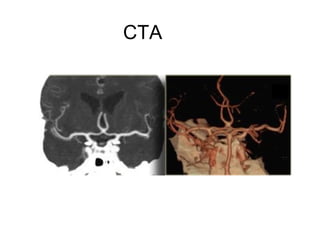

CTA

CT Angiography

• For assessment of intracranial and extracranial

circulation

• Can demonstrate thrombi

• Timed bolus of contrast for vessel enhancement

• Can guide decision regarding intraarterial or mechanical

thrombolysis by quantifying clot burden

Normal CT Angiography